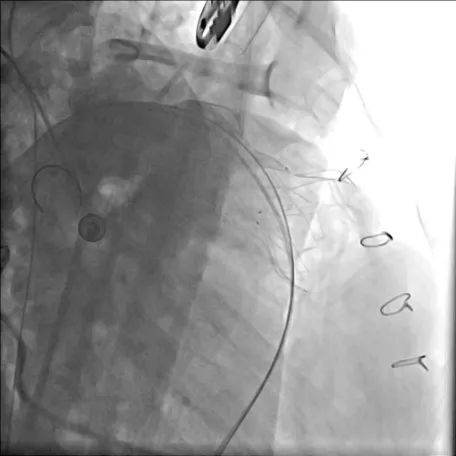

术后造影显示无明显肺动脉瓣反流(左图为患者1,右图为患者2)